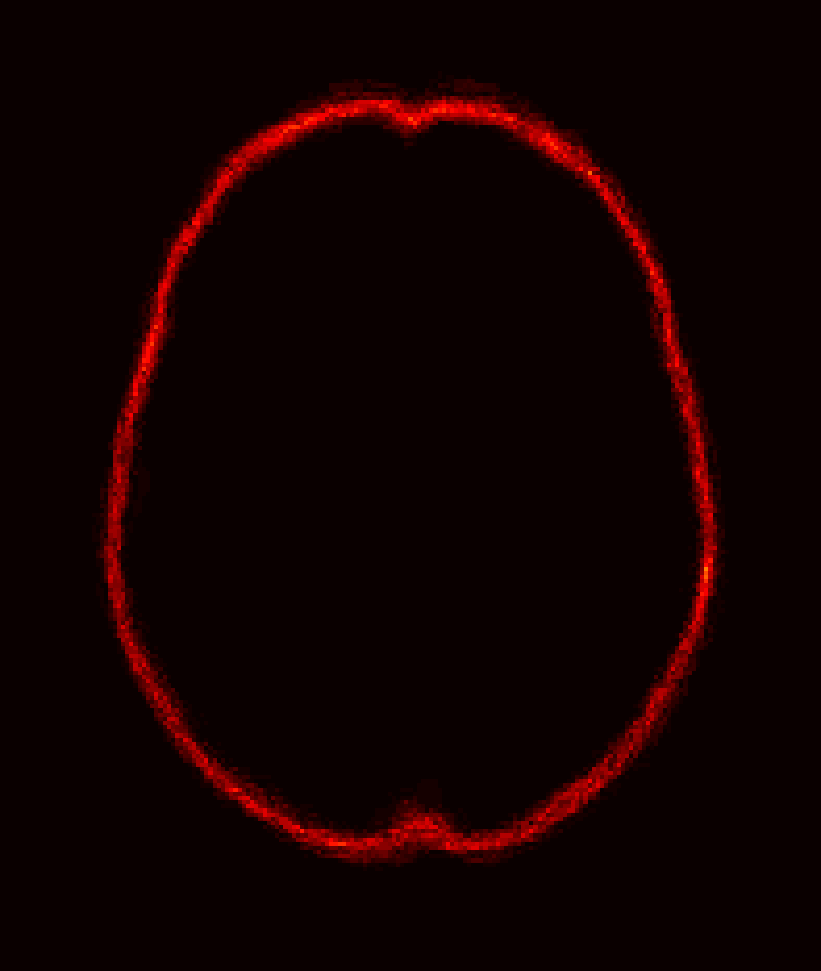

Fig. 9 (left) visualizes the average brain mask errors for IBSR and LPBA40. All images are first affinely registered to the atlas. Then we transform the gold-standard expert segmentations as well as the automatically obtained brain masks of the different methods to atlas space. We compare the segmentations by counting the average over- and under-segmentation errors over all cases at each voxel. This results in a visualization for areas of likely mis-segmentation. Our PCA model, ROBEX, BEaST (BEaST*) and BET perform well on these two datasets. Compareed to our model, ROBEX, BEaST (BEaST*) and BET show larger localized errors, e.g., at the boundary of the parietal lobe, the occipital lobe and the cerebellum. While MASS, BSE and CNN perform well on the LPBA40 dataset, they perform poorly on the IBSR dataset. This is in particular the case for the CNN approach.

Finally, Fig. 9 (right) shows the average segmentation errors on the BRATS and TBI datasets: our PCA method shows fewer errors than most other methods in these two abnormal datasets. MASS also shows few errors, while ROBEX, BEaST (BEaST*) and BET exhibit slightly larger errors at the boundary of the brain. CNN and BSE particularly show large errors for the BRATS dataset presumably again due to the coarse resolution of the BRATS data.

Figure 9: Examples of 3D volumes of average errors for the normal IBSR and LPBA40 datasets, as well as for the pathological BRATS and TBI datasets. For IBSR/BRATS, we show results for BEaST*. Images and their brain masks are first affinely aligned to the atlas. At each location we then calculate the proportion of segmentation errors among all the segmented cases of a dataset (both over- and under-segmentation errors). Lower values are better (a value of 0 indicates perfect results over all images) and higher values indicate poorer performance (a value of 1 indicates failure on all cases). Clearly, BSE and CNN struggle with the BRATS dataset whereas our PCA method shows good performance across all datasets.